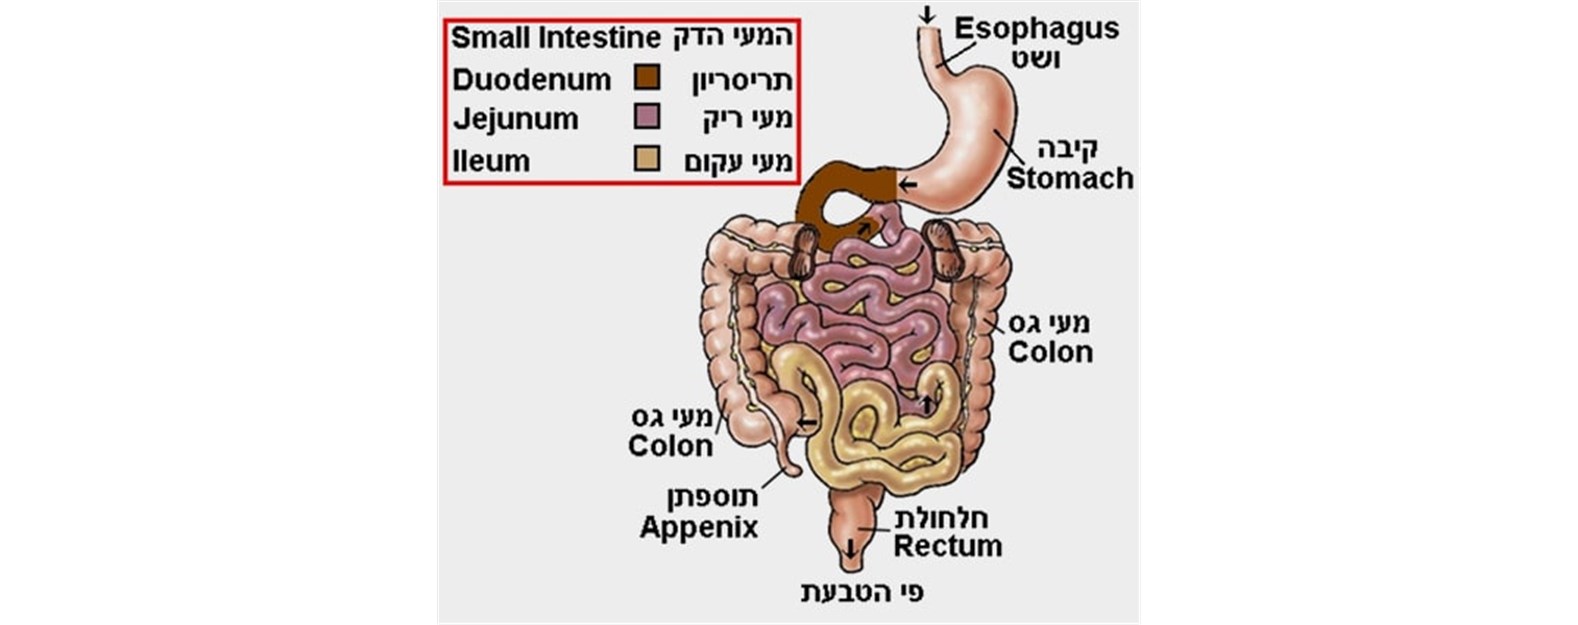

תסמיני המחלה נגרמים על ידי התהליך הדלקתי הכרוני במערכת העיכול. מחלת קרוהן יכולה לפגוע בכל חלק ממערכת העיכול, מהפה ועד לפי הטבעת, אך המעי הדק מעורב בלפחות 70% מהחולים. לפחות ב-40% מהחולים זהו גם המקטע היחיד המעורב במחלה. אורכו של המעי הדק הוא כ- 7 מטרים בממוצע, ורק חלקו הקטן (המכונה איליום סופי – אזור החיבור למעי הגס) ניתן לבדיקה באמצעות קולונוסקופיה. לכן בחלק משמעותי מהחולים במחלה, הקולונוסקופיה יכולה להיות תקינה לחלוטין, ויש צורך באמצעי אבחנתי אחר שיכול לסרוק את כל המעי הדק, ולא רק את חלקו הסופי.